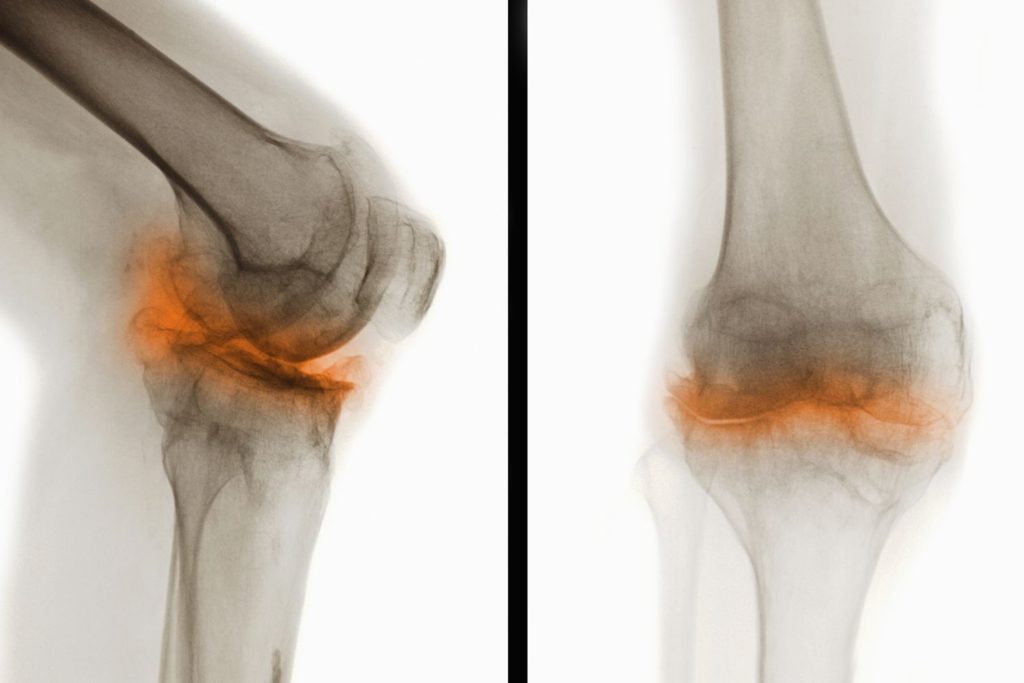

Деформирующий остеоатроз

Наиболее распространенная болезнь коленных суставов. По статистике, каждый третий человек, имеющий проблемы с коленями, страдает именно от этой патологии. Деформирующий остеоатроз обычно развивается в возрасте более 40 лет. Чаще всего страдают женщины, спортсмены, лица с избыточной массой тела и люди, выполняющие тяжелую физическую работу.

Деформирующий гонартроз – это хроническое дегенеративно-дистрофическое заболевание, ведущее к постепенному разрушению внутрисуставных хрящей. При отсутствии адекватной терапии патология ведет к прогрессирующему снижению работоспособности и даже инвалидности. Но правильное своевременное лечение не позволяет избавиться от остеоартроза, а всего лишь замедляет его развитие.

На начальных стадиях симптомы этой болезни коленного сустава слабо выражены или вовсе отсутствуют. Со временем больного начинают беспокоить ноющие боли в суставе, возникающие после резкого вставания со стула, во время ходьбы, при подъеме по лестнице. Вскоре заболевание приводит к выраженному нарушению подвижности колена.

Таблица 2. Степени развития гонартроза

| Степень | Клиническая картина | Лечение | Течение и прогноз |

| I | Периодические несильные боли, исчезающие после отдыха. Незначительная, быстропроходящая отечность. Отсутствие деформации | Коррекция образа жизни, лечебная физкультура, ношение ортопедической обуви. Обезболивающие мази, хондропротекторы в виде таблеток | Не мешает человеку вести привычный образ жизни. Вызывает некоторый дискомфорт при физических нагрузках. При адекватном лечении не прогрессирует и не приводит к осложнениям |

| II | Частые выраженные боли, характерный хруст. Появление скованности, затрудненности при движениях. Начальная деформация коленных суставов | ЛФК, физиотерапия, массаж. Применение обезболивающих, противовоспалительных средств, хондропротекторов, препаратов кальция. Фонофорез с гидрокортизоном или внутрисуставное введение кортикостероидов | Затрудняет выполнение простых действий и мешает человеку вести привычный образ жизни. Правильное консервативное лечение улучшает состояние больного, приостанавливает разрушение суставных хрящей |

| III | Постоянные сильные боли при ходьбе, резкое ухудшение подвижности колена. Заметное увеличение объема, деформация сустава | Лекарства, ЛФК, медикаментозная терапия малоэффективны. Они незначительно облегчают самочувствие человека, но не помогают полностью избавиться от неприятных симптомов | Вызывает резкое снижение трудоспособности. Чтобы избавиться от постоянных болей, снова начать нормально ходить, человеку требуется операция |